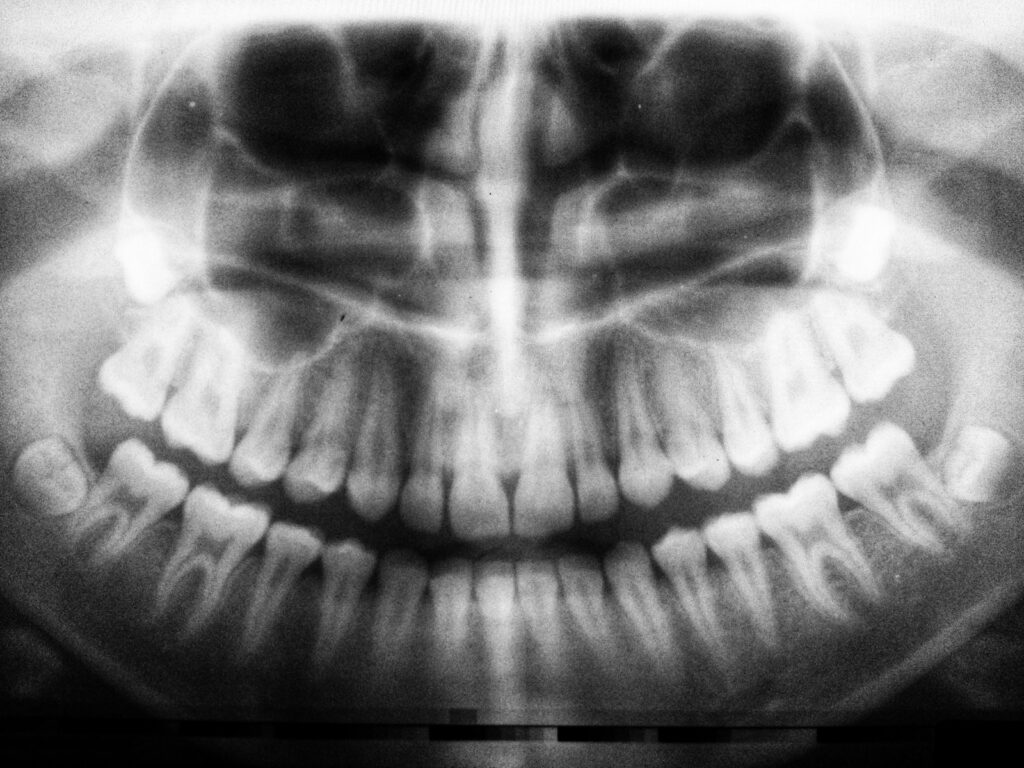

Kenosha Family Dentistry uses advanced digital radiographs to provide clear, detailed images of your teeth and jaw. This technology allows us to detect issues early while using significantly less radiation than traditional X-rays. Digital imaging also enables faster results, so we can diagnose concerns accurately and create treatment plans without delay.

teeth X-ray